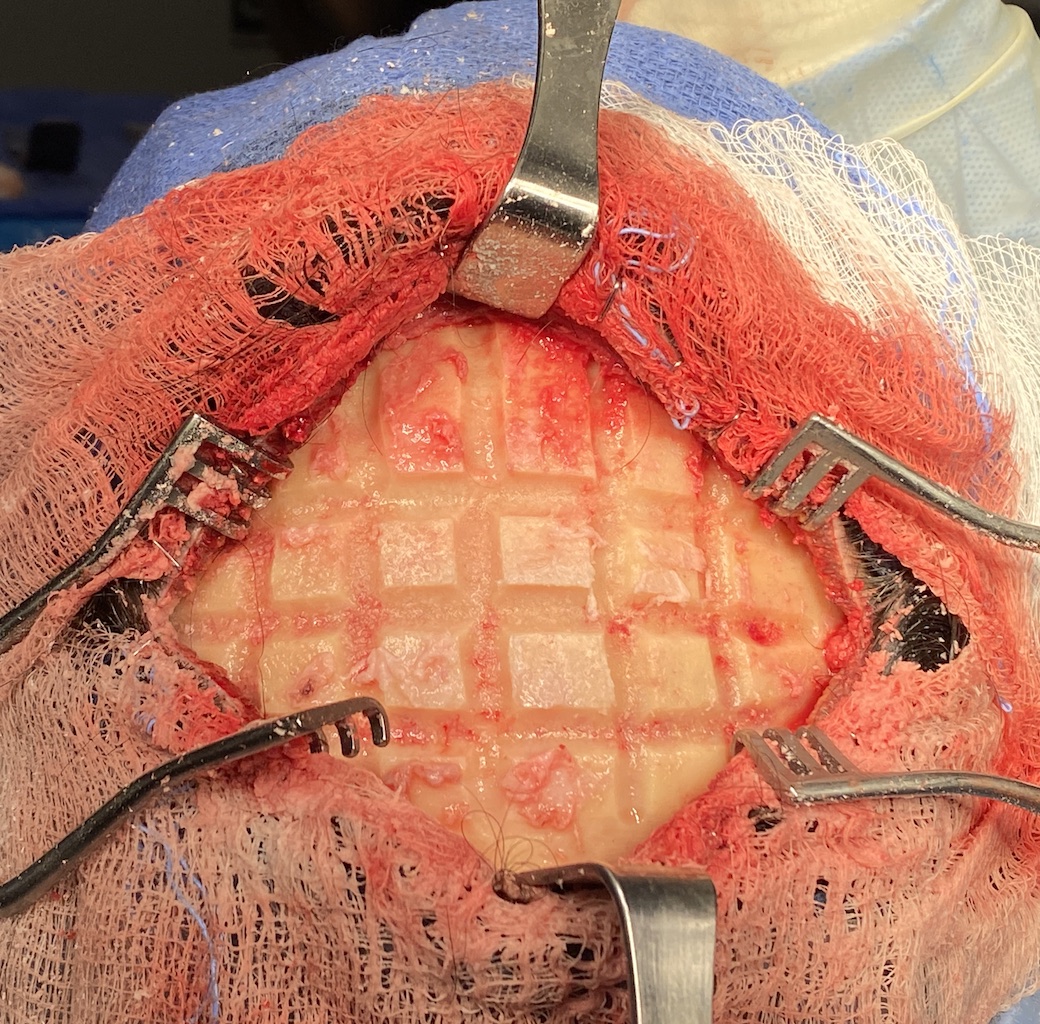

Patient 45

Desire for reduction in height of top of head.

Top of head skull reduction by removal of the outer cortical bone layered by a grid burring technique.

Desire for reduction in height of top of head.

Top of head skull reduction by removal of the outer cortical bone layered by a grid burring technique.